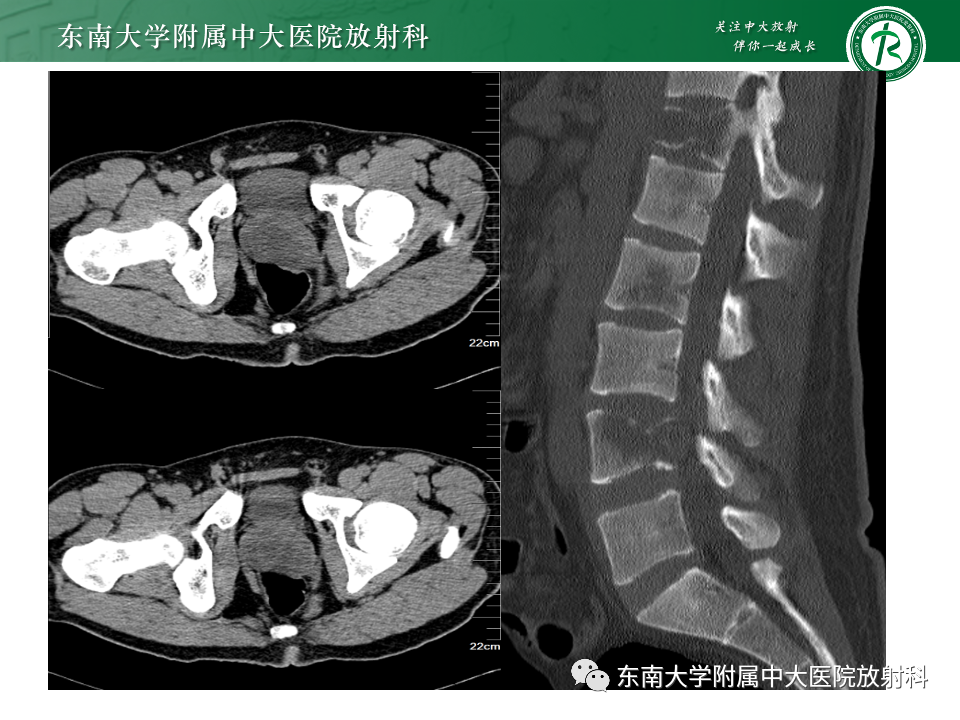

病史

男,68岁,发烧伴肛周疼痛1月

既往史:10月前于外院行“直肠癌根治术”,病理为中分化腺癌

实验室检查:白细胞计数:8.05×10^9/L;红细胞计数:3.84×10^12/L↓;血红蛋白:118g/L↓;中性粒细胞比率:84.1%↑;淋巴细胞比率:10.5%↓

B超提示:前列腺左侧叶低回声团,占位?